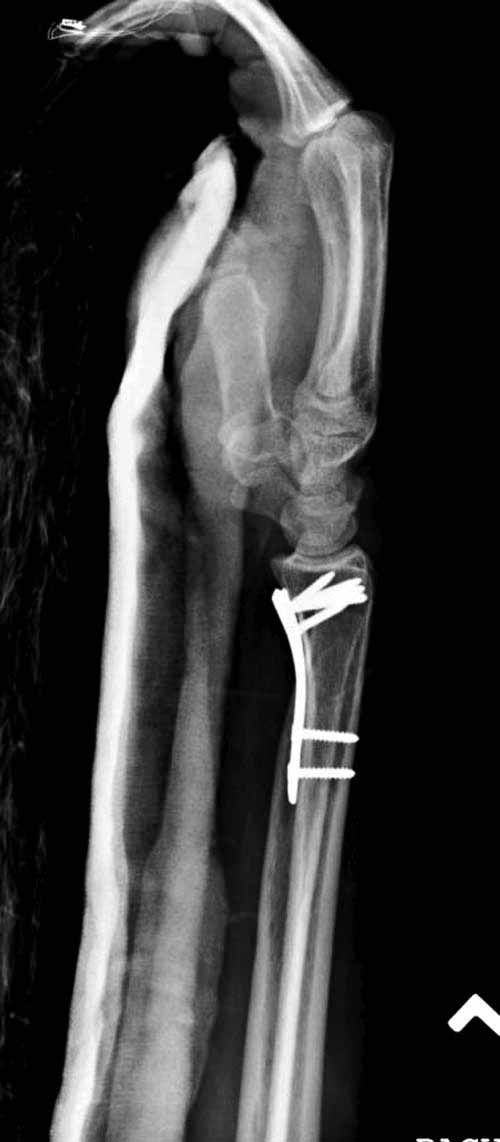

Сегодня все компании: Synthes, Stryker, Zimmer, Acumed, TriMed и т.д. имеют пластины для фиксации дистального перелома лучевой кости. На снимке метод фиксации дистальных переломов, справа Stryker, а слева пластина Synthes,

женщина 58 лет, политравма.

Нет не в вывихе, т. К. Из-за спицы проведенной через обе кости предплечья, то ротационные движения и подвижность локтевой кости резко ограничены, это может в некоторых проекциях расцениваться как подвывих, если найду покажу финальный снимок, там все рентгенологические показатели восстановлены.